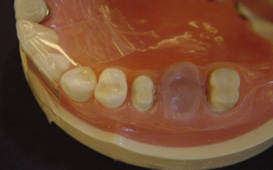

單顆雙植體 案例一

植體設計

寬直徑 vs 一般直徑